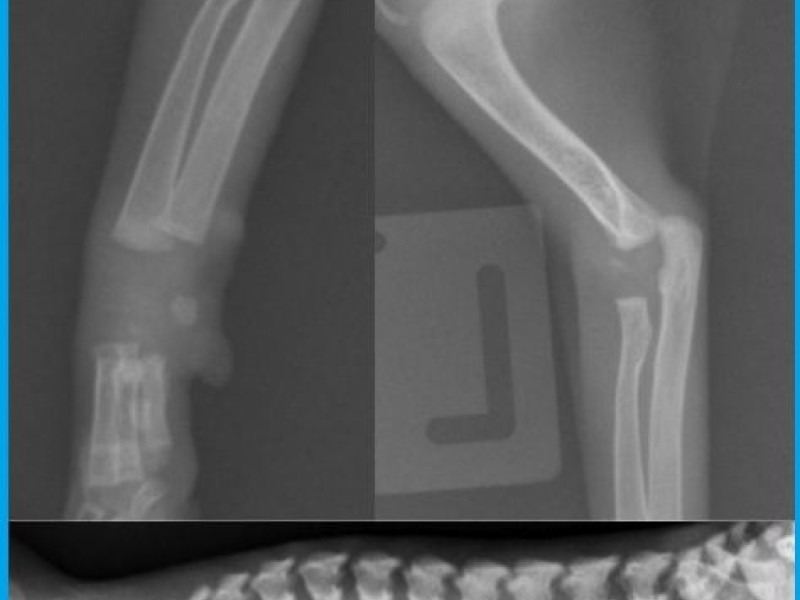

Des radiographies du squelette révèlent un retard d'ossification des épiphyses de manière symétrique et généralisée. Les os du carpe sont absents.

Une radiographie d'un châton de la portée et du même âge a été prise en comparaison. Cf la deuxième radio.

Discussion: Des anomalies du squelette, comme un retard de maturation et une dysgénésie épiphysaire sont caractéristiques d'une hypothyroïdie congénitale, plus tard les animaux ressemblent à des nains disproportionnés.

Un retard de maturation épiphysaire est observée dans les

corps vertébraux et les os longs des chatons, accompagné d'un retard de maturation des os du carpe et du tarse. La dysgénésie épiphysaire se caractérise par un délai d'apparition des foyers d'ossifications épiphysaires, et en absence de supplémentation, les épiphyses apparaissent fragmentées avec des foyers de minéralisation dispersés. Normalement, les épiphyses se développe d'un centre unique. Plus tard, cette malformation hypophysaire conduit à des arthropathies dégénératives.